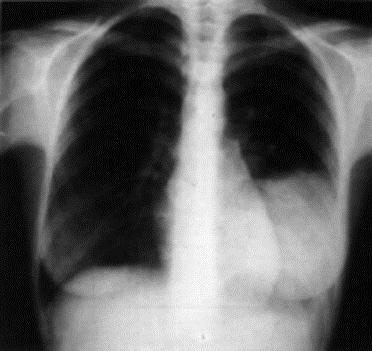

1.2.1 Radiografia (tomografia, broncografia)

Metodo diagnostico prevalente, eventualmente completato con tomogramma delle parti dubbiose o broncografia (a contrasto).